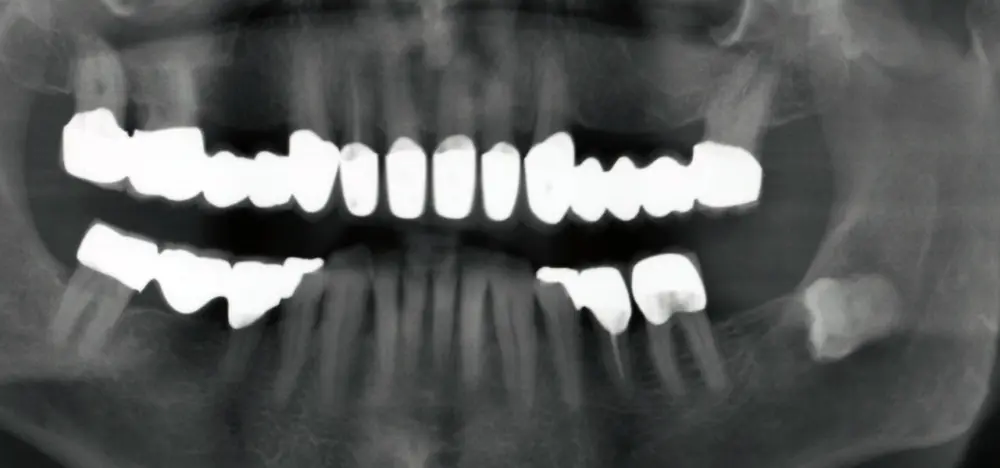

Eine professionelle Zahnreinigung (PZR) ist hilfreich, weil sich auf gereinigten Zähnen Plaque (Zahnbelag) leichter im Zaum halten lässt; Plaquefreiheit von eigener Hand herzustellen, ist mühsamer. Stellt der Zahnarzt einen Code 3 (Zahnfleischtaschen von 3,5 bis 5,5 mm) oder sogar Code 4 (Zahnfleischtaschen tiefer als 5,5 mm) fest, muss allerdings eine gründliche Untersuchung durchgeführt werden, um das Ausmaß der Erkrankung und den Behandlungsumfang feststellen zu können. Dafür werden die Zahnfleischtaschen und der Gewebeverlust an allen Zähnen gemessen und Röntgenbilder angefertigt.

Eine erfolgreiche Behandlung der parodontalen Entzündung kann nicht nur die lokalen Symptome der Erkrankung des Zahnhalteapparats und damit Zahnverlust vermindern (s. Abb. 3 u. 4), sondern auch die Stoffwechseleinstellung verbessern. Die Reduktion des HbA1c-Werts lag bei Typ-2-Diabetikern drei Monate nach einer nichtchirurgischen Parodontitisbehandlung zwischen 0,4 und 0,5 Prozent, was durchaus nennenswert ist.